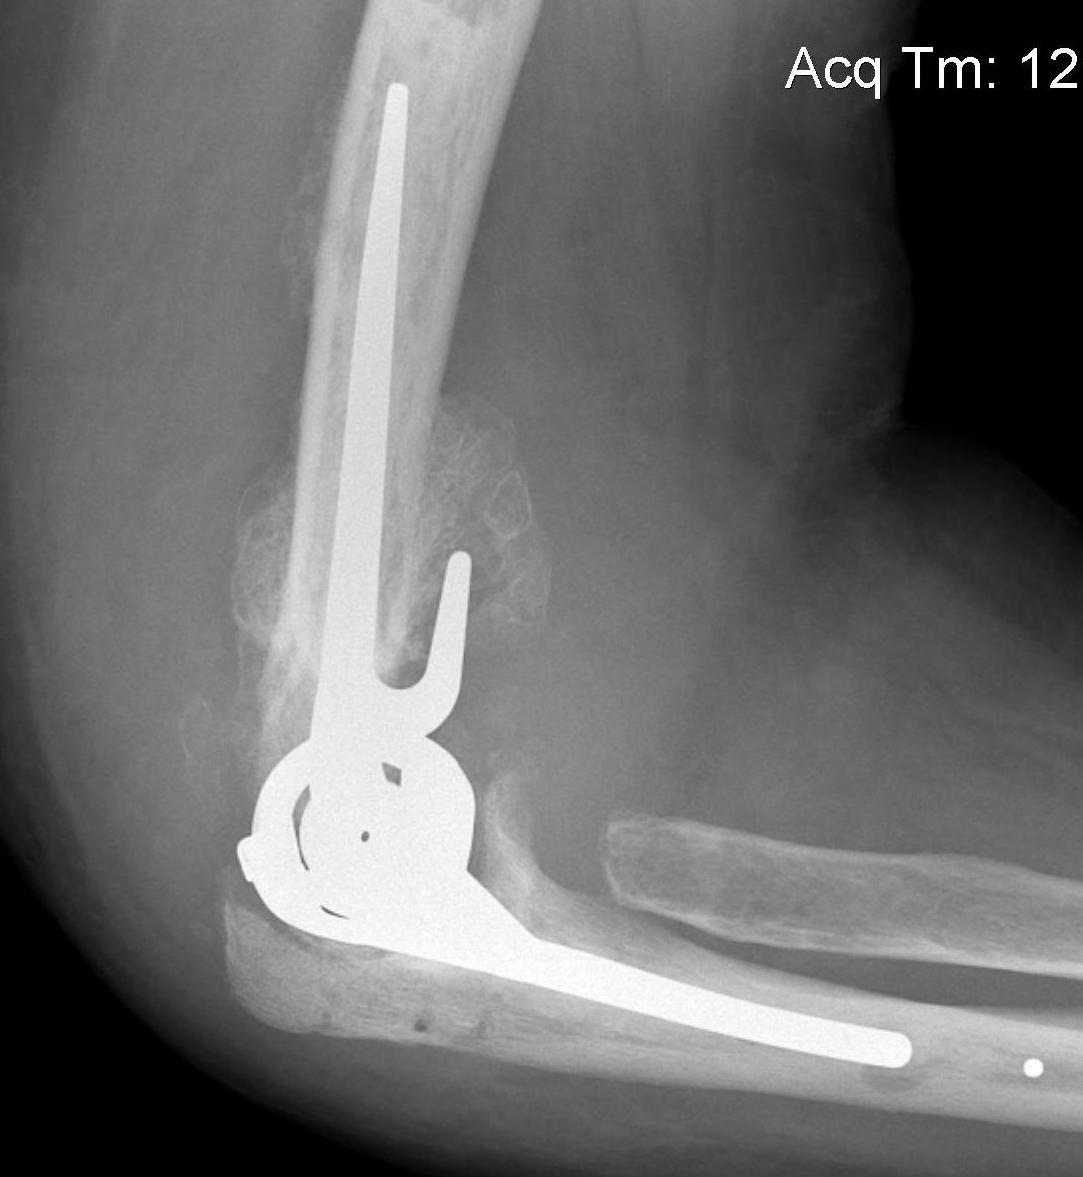

Aseptic Loosening

- systematic review of 3000 TEA

- loosening rates 10% for unlinked and 14% for linked prosthesis

Results

- revision with allograft - prosthesis composite

- 25 patients

- one nonunion / one malunion

- 84% TEA survival

Ulna allograft - prosthetic revision TEA